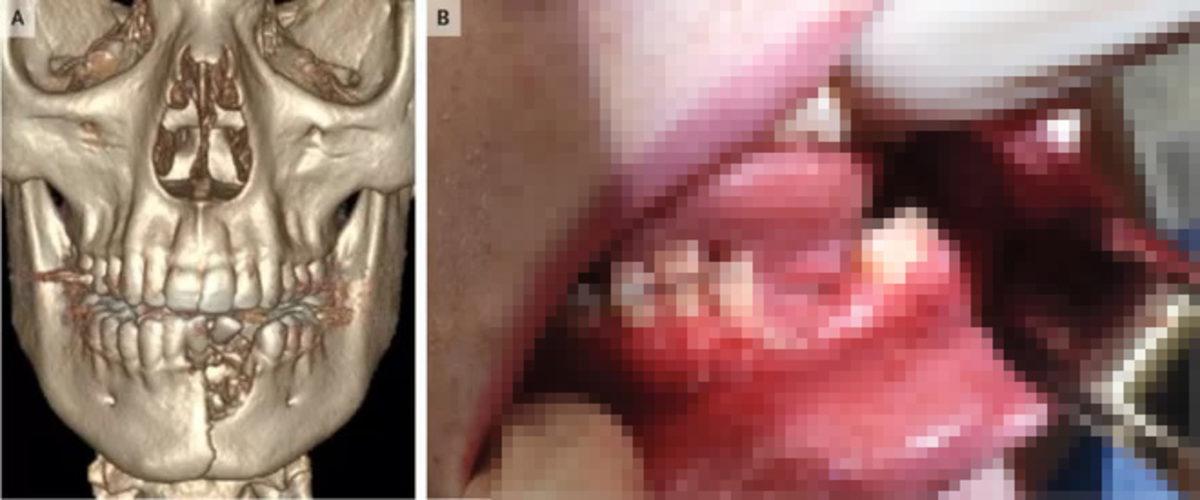

Amerika'nın Utah eyaletinde yaşanan bir olayda ise 17 yaşındaki bir gencin ağzında elektronik sigara patladı. Patlamanın şiddeti çocuğun çenesini kırmaya, dişlerini dökmeye ve talihsiz gencin ağzında geniş yaraların açılmasına neden oldu. Eletronik sigarası ağzında patlayan genç, yaklaşık 2 saat sonra sağlık merkezine geldi. Salt Lake City Çocuk Hastanesi'nde talihsiz gence ilk müdaheleyi yapan Doktor Katie Russell, yaşanan olayın boyutlarını "Bu genci gördüğümde, bir elektronik sigaranın neler yapabileceği hakkında hiçbir fikrim yoktu. Çenenizi kırmak için çok fazla güç gerekiyor." diyerek gözler önüne serdi.

Yapılan müdahelelerle ilgili de açıklamalarda bulunan Russell, diş yuvalarının fazlasıyla tahriş olduğunu tespit ettikleri için bazı dişleri de çektiklerini, kırılan çenesini sabitlemek içinse diş etlerinin altına bir plak yerleştirdiklerini söyledi. Talihsiz gencin çenesinin düzelmesinin 6 haftayı bulabileceğini söyleyen Russel, çenenin şimdilik kapanmadığını ancak bu durumun normal olduğunu, kalıcı bir hasar beklemediklerini söyledi.